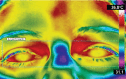

Methods: Four asymptomatic women were evaluated for three consecutive menstrual cycles. Using thermography, the temperature of breasts and eyes was measured as indirect reference of core body and room temperatures. To analyze the thermal behavior of the breasts during the cycle, the core body and room temperatures were normalized by means of a mathematical equation.

Results: We performed 180 observations and the core temperature had the highest correlation with the breast temperature, followed by room temperature. The proposed prediction model could explain 45.3% of the breast temperature variation, with variable room temperature variable; it can be accepted as a way to estimate the reference breast temperature at different room temperatures.

Conclusion: The average breast temperature in healthy women had a direct relation with the core and room temperature and can be estimated mathematically. It is suggested that an equation could be used in clinical practice to estimate the normal breast reference temperature in young women, regardless of the day of the cycle, therefore assisting in evaluation of anatomical studies.